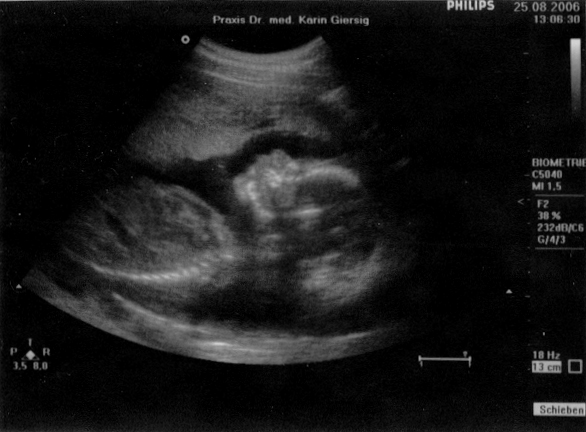

Ultraschall vom 26. Juni 2006

Scheitel-Steiß-Größe: 6,5 cm

Gesundheitszustand: einwandfrei

Geschlecht: unklar